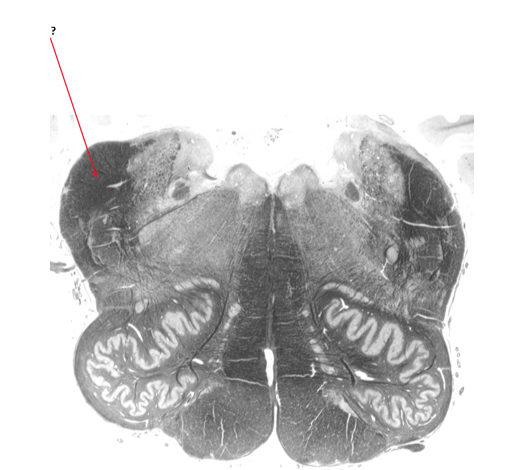

Name this and state its function.

Inferior cerebellar peduncle.